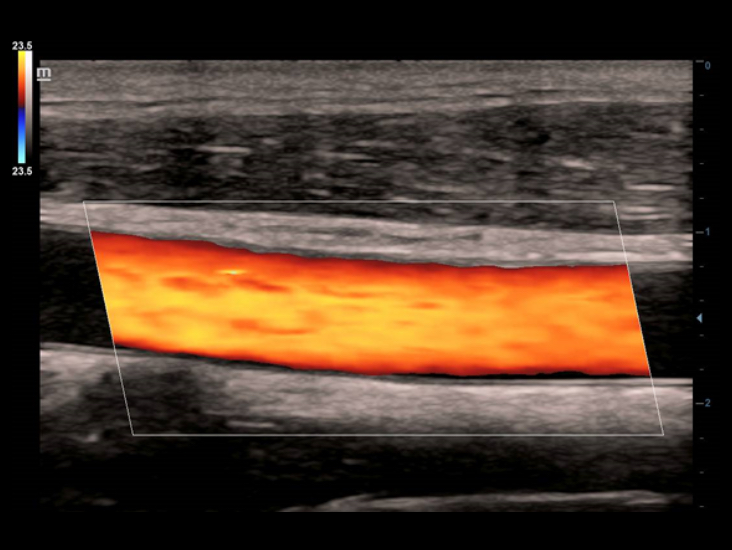

Geleneksel d?nÞ?tÞrÞcÞler ile kar??la?t?r?ld???nda ComboWave d?nÞ?tÞrÞcÞlerin, akustik spektrumu ?nemli ?l?Þde optimize etmek ve akustik empedans? azaltmak i?in yeni bir kompozit piezoelektrik materyal tÞrÞnÞ kulland?klar? g?rÞlÞr. Mindray'in benzersiz 3T teknolojisi ile entegre edilen ComboWave lineer d?nÞ?tÞrÞcÞler, tiroid, meme, vaskÞler ve daha fazla alanda yÞksek g?rÞntÞ ??zÞnÞrlÞ?Þ ve tekdÞzeli?i ile ÞstÞn performans? deneyimlemenizi sa?lar.

Ak?ll? Takip, yaln?zca tek dokunu?la ?al??arak, vaskÞler g?rÞntÞleme i?in h?zl? ve ak?ll? optimizasyon sa?lar. Otomatik takiple, Renk, GÞ? ve PW spektrumunu optimize edebilir ve zaman alan ad?mlar? azaltabilir. Bu nedenle, vaskÞler muayene i? ak??? optimum g?rÞnÞmle basitle?tirilir.